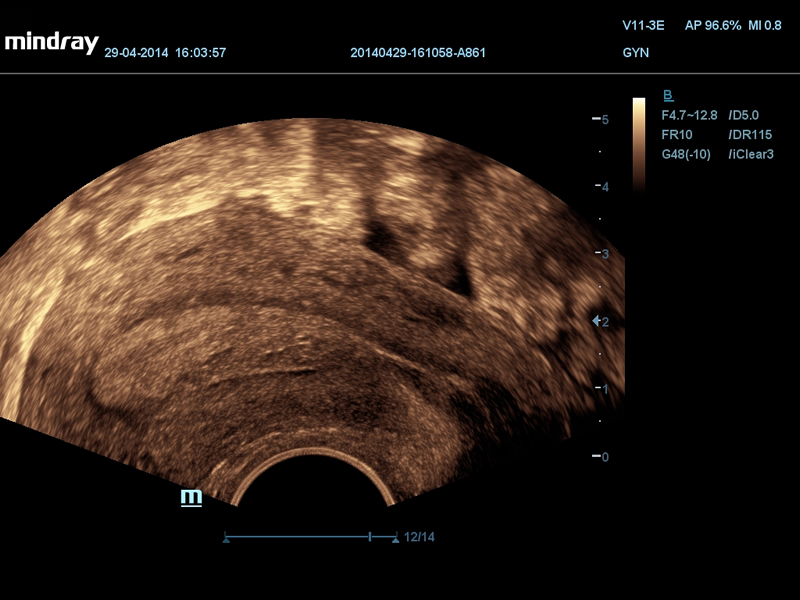

ЭВ-утолщение эндометрия